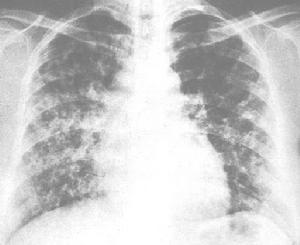

亞胺培南-西拉司丁鈉男,59歲。因慢性喘息性支氣管炎病史20餘年,發作半月而入院。患者半月前因受涼後咳嗽、咳痰及喘息症狀加重,在單位衛生所給予抗感染及對症治療,先後套用頭孢唑啉鈉、舒巴坦鈉/頭孢哌酮鈉等藥物治療,療效不佳,轉入我院。查體:體溫36.8℃,脈搏120/min,血壓150/90mmHg,呼吸26/min。口唇顏面明顯發紺,四肢、顏面水腫。桶狀胸,雙肺叩診呈過清音,聽診可聞及廣泛乾性濕囉音,心率120/min,可聞及早搏;肝肋下2cm。X線胸片示雙肺透光度增強,肋膈角增寬,肺紋理增重,右下肺高密度片狀陰影,右肋膈角不清;右下肺動脈17mm,肺動脈段突出。血常規:紅細胞4.24×1012/L,白細胞12.7×109/L,中性粒細胞0.88;血氣分析:pH7.364,PO233mmHg,PCO262mmHg,HCO3-34.1mmol/L。入院診斷:慢性喘息型支氣管炎急性發作期;右下肺炎;Ⅱ型呼吸衰竭;慢性肺原性心臟病,心功能Ⅳ級。